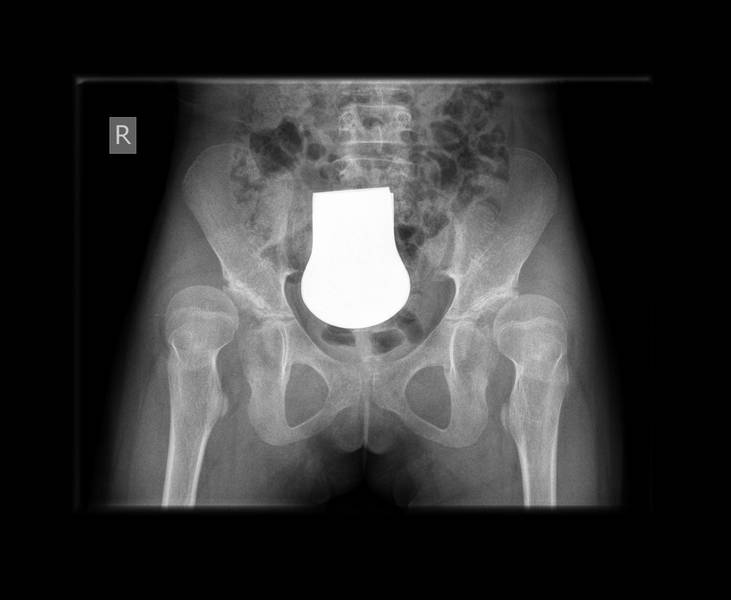

Die Beispielbilder zeigen eine zunehmende Auswanderung beider Hüftköpfe eines Mädchens im Alter von 9 Jahren. Gut sind auch die steilen Pfannendächer zu sehen. Es ist zu erwarten, dass beide Hüftköpfe im weiteren Verlauf vollständig ausrenken werden. Die Schenkelhälse wurden mit einer winkelstabilen Platte umgestellt (DVO) und die Pfannen wurden mit Knochen aus den Schenkelhälsen wieder rekonstruiert (AC-Plastik).

Hüftkopf-Verschraubung bein Hüftkopfgleiten (Epiphyseolysis capitis femoris / ECF)

In der Puperbät kann es bei manchen Jugendlichen dazu kommen, dass die Hüftkopfkappe in der Wachstumsfuge vom Schenkelhals abrutscht. Wenn der Kopf nicht wieder vollständig reponiert wird, so kann es zu einen zu einer Durchblutungsstörung mit Abbau des Kopfes kommen. Zum anderen kann eine Fehlstellung resultieren, die später zu Beschwerden führen kann. Ziel der Operation ist also die vollständige Wiederherstellung der normalen Anatomie (Reposition) und die Verhinderung eines erneuten Abgleitens. Da in bis zu 30% die zweite Seite auch abrutschen wird, muss sie bei der Operation gleich mitfixiert werden.

Erfahrenen Operateuren ist es möglich, die Reposition und die Fixierung minimalinvasiv durch eine Hohlschraube durchzuführen. Die Nachbehandlung erfolgt durch Entlastung mit Unterarmgehstützen für 6 Wochen.

Die Beispielbilder zeigen einen Hüftkopfgleiten mit einem Abrutschwinkel von 50°. In der normalen Beckenübersichtsaufnahme ist diese Verletzung häufig nur sehr schlecht zu sehen. Die geschlossene Operation mit minimalinvasiver Fixierung durch Hohlschrauben führte zur vollständigen Ausheilung. Die Schrauben wurden nach Wachstumsabschluß (geschlossene Wachstumsfugen) wieder komplikationslos entfernt.